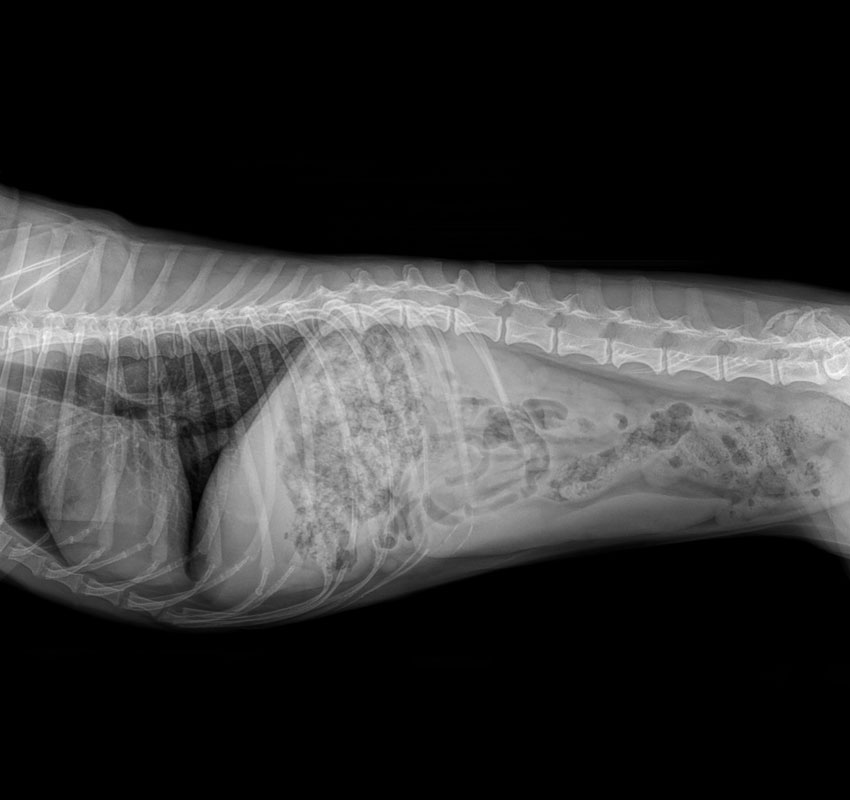

Digital X-Rays Digital x-rays are quite the advancement from their predecessors. They emit much less radiation, take less time to produce, and can be easily shared as a digital file between veterinarians and pet owners. Digital x-rays are used for the following:

• Fractures and other orthopedic diseases or abnormalities

• Bladder stones

• Heart, lung, or liver disease

• Intestinal abnormalities

• Stomach issues

• Tumors

• Ingested foreign objects